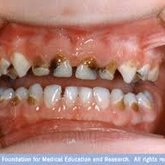

We make it a priority to incorporate the latest in dental technology in everything we do at our practice. ...